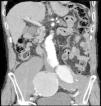

The patient was an 86-year-old man who was taking 2 medications for hypertension. He had a history of several months of low back pain that radiated to right thigh, for which symptomatic treatment provided partial relief. His rheumatologist had ordered thoracolumbar magnetic resonance imaging (MRI), but it was not performed because, prior to the scheduled date, the patient went to the emergency department with an increase in the intensity of the pain. Laboratory analyses showed a hemoglobin level of 8.4g/dL, lactate dehydrogenase of 318U/L, creatinine of 1.29mg/dL, C-reactive protein of 6.16mg/dL, erythrocyte sediment rate of 24mm/h and mild hypoproteinemia. There was no evidence of hemodynamic instability. He underwent abdominopelvic computed tomography (CT) with intravenous contrast, which revealed isolated bilateral iliac aneurysms>6cm (Fig. 1) with contained rupture of the aneurysm on the right (Fig. 2), which displaced the psoas muscle (Fig. 3) and perforated the ipsilateral iliac bone (Fig. 4). The patient underwent aortobifemoral bypass but, unfortunately, he died during the postoperative period.

Isolated iliac aneurysms, without an associated aortic aneurysm, are rare.1 They are relatively difficult to identify, as up to 40% of them may present with rupture.2 The incidence rate of extraspinal causes of sciatica is low.3 Likewise, chronic rupture of an aneurysm constitutes a peculiar entity. All these circumstances coming together result, in most cases, in an erroneous or late diagnosis.4 It is usually a dorsolateral rupture toward the anterior insertions of the psoas muscle, which contains the hematoma, avoiding massive extravasation, but not the infiltration of the roots of the lumbosacral plexus. This produces chronic low back pain that radiates to the lower limb,5 this being the most common presentation.6 The diagnosis can be based on abdominal CT,7 and lumbar MRI (parasagittal slices).7,8 The aneurysm may undergo secondary acute rupture at any time.4 This case serves to remind us, in our routine practice, that an aneurysm may be involved in the symptoms of sciatica.9